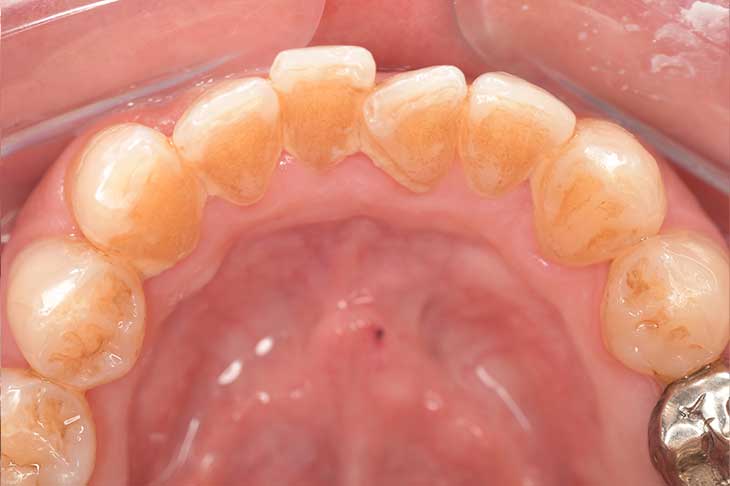

CASE 4

Before

After

基本情報

| 年齢・性別 | 52歳・女性 |

|---|---|

| 主訴 | クリーニングしたい |

| 治療内容 | スケーリング・PMTC |

| 治療期間 | 60分 |

| 治療費 | 約7,000円 |

| リスク・副作用 | 知覚過敏、歯肉退縮 |

| 治療方針 | 歯石とステインを除去して、今後は定期検診でのクリーニングと併せてガムピーリングやホワイトニングを行います。 |

| 担当者所見 | 歯肉の色素沈着が目立つため、ガムピーリングを行いながらホワイトニングを行うことをおすすめします。 |